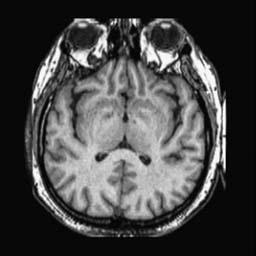

To demonstrate the effectiveness and efficiency of the proposed image fusion method , we conduct a set of comparative experiments on three image datasets. The first is composed by 8 pairs of multi-modal medical images and the second one contains 15 pairs of multi-focus gray or color natural images. These two datasets are often used in many related papers and some examples are shown in Figure 3(a) and Figure 3(b). The third one is a new multi-focus cervical cell image dataset collected by ourselves, which consists of 15 groups of color images and each group contains a series of multi-focus cervix cell images with size of or , etc. Some source examples are shown in Figure 3(c). Our source code implemented in C++ along with the new multi-focus cervical cell image dataset is available online.

We first evaluate the performance of the proposed method under varying total number of octaves and number of layers sampled per octave. The fused images of a pair of multi-modal medical images with different and are shown in Figure 4. In this example, on the one hand, when only 1 or 2 octaves are involved in constructing the DoG pyramid, the fused images fail to keep the integrity information of large size objects (e.g. eyeballs), while by increasing the value of , the integrity information of eyeballs is preserved. On the other hand, although not as significant as the increase of octave numbers , the fused image can contain more details by the increase of layer numbers . The corresponding objective quality metrics are shown in Figure 5. As shown in Figure 5(a), most of the metric values are improved as the number of octaves increases with the fixed layer numbers 3 in the global tendency and each of them tends to be stable when the number of octaves is 5. To get a relatively good quality from Figure 5(b), we can notice that some of the metric values can get a good performance when the number of layers is 3, such as the MI, SSIM, QI and VIF, though there are only a little change of all the metric values by increasing the number of layers with the fixed octave numbers 5. Because it will result in more computation burden with the increase of the value and , and for different kinds of source images, there are different performance with the diverse parameter settings. To get a trade-off between them in our experiments, we set for the multi-modal dataset, for the natural datasets and for the multi-focus cell dataset, respectively.

Figure 6 shows the fused images obtained by different methods with the multi-modal source images shown in Figure 3(a). As shown in these figures, the proposed method can produce images which preserve the complementary information of different source images well. Moreover, due to the scale-invariant structure saliency selection, our method can keep the integrity information of large size objects and the visual details simultaneously. Although the fused image generated by other methods can also capture the details to some extent, all of them fail to keep the integrity information of large size objects such as the eyeballs. Furthermore, from Figure 6(k)-6(t), the DTCWT, GFF, IM and NSCT methods may decrease the brightness and contrast while the proposed method can preserve these features and details without producing visible artifacts and brightness distortions.